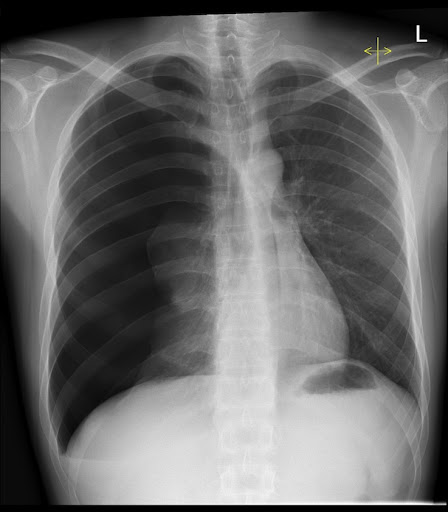

What's the Diagnosis?

Guess 1 / 5